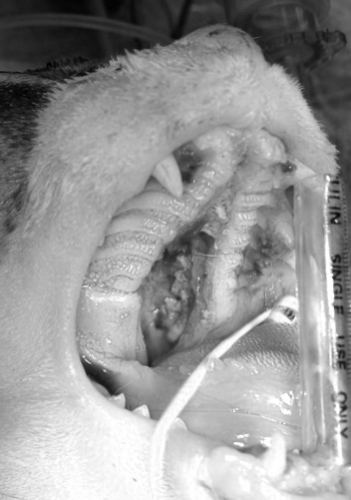

左の写真は右下からの正面像で、上顎の歯の後ろから喉に至る部分が完全に避けて鼻の穴の奥が口から見えていしまっている状態です。右写真は裂けてしまった上顎の断面が痛々しい写真です。ここまで重度のものになるとまったく食事を摂ることができないだけではなく呼吸の障害も生じるため、早急に手術が必要になります。